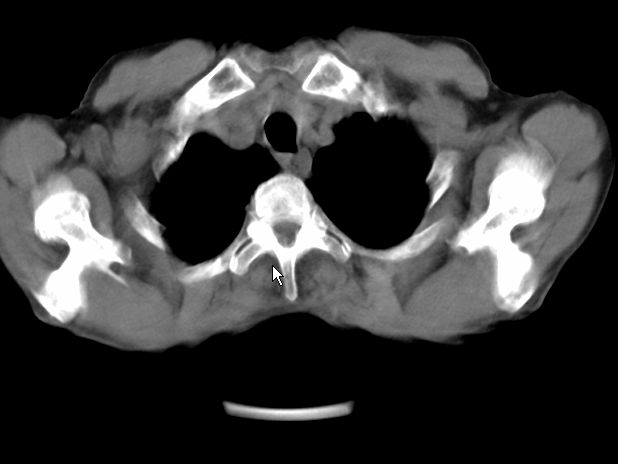

请大家看看是什么性质的。炎性病变首先考虑哪一种炎症。

支持右肺上叶前段\\下叶内基底段感染,建议抗炎治疗后复查,除外结核.

支持右肺上叶前段\\下叶上段感染,建议抗炎治疗后复查,除外结核.

支持右肺上叶前段、下叶内基底段感染,建议抗炎治疗后复查,除外结核.

右肺上叶前段及下叶内基底段感染性病变;建议抗炎治疗后复查。

楼主说是炎症,凭啥?典型的周围型肺癌(腺癌可能性大),肝内可能已有转移,强化看看吧。